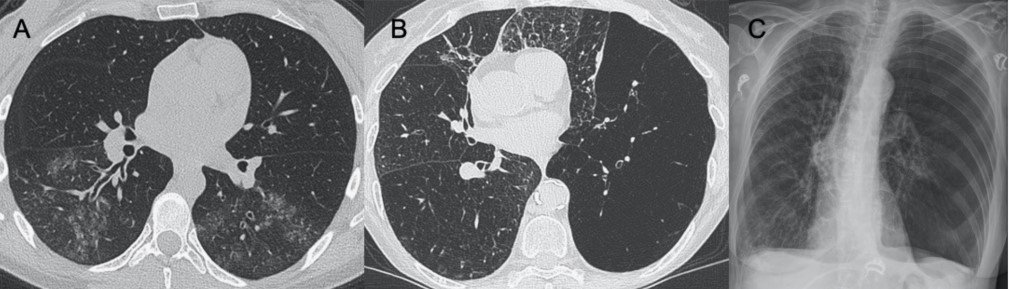

● CXR:雙側網狀結節狀影伴實變區,通常在下葉。

● CT:GGO多灶性實變和彌漫性區域,還可能觀察到淋巴結病變、空洞形成、胸腔積液。

圖3 圖(A-C)顯示了一例與COVID-19間質改變相似的甲型流感病例:GGO主要分布在胸膜下和雙側,呈小葉周圍性分布。圖(D)為同一患者的仰臥位胸片,可見彌漫性間質受累。